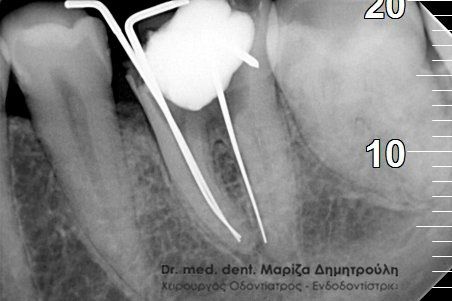

ΠΡΙΝ ΜΕΤΑ

Η ασθενής παραπονιόταν για συνεχή πόνο στο συγκεκριμένο δόντι, το οποίο είχε απονευρωθεί πριν χρόνια. Μετά από τη λήψη ακτινογραφίας διαπιστώθηκε οτι στην πρώτη ενδοδοντική θεραπεία δε είχε μετρηθεί σωστά το μήκος της ρίζας του δοντιού. Μετά την επανάληψη της απονεύρωσης το δόντι καθαρίστηκε και εμφράχθηκε σε όλος το μήκος της ρίζας, όπως δείχνει και η δεξιά αντινογραφία.